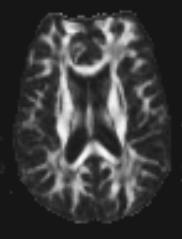

Fractional anisotropy image. White pixels (dots) correspond to high values of fractional anisotropy (FA). Dark pixels correspond to low values of FA. White matter consists of axons, which serve as barriers for free water diffusion, and explains the high anisotropy which is bright compared to cortex where there is less structure and more free diffuse resulting in lower sign.